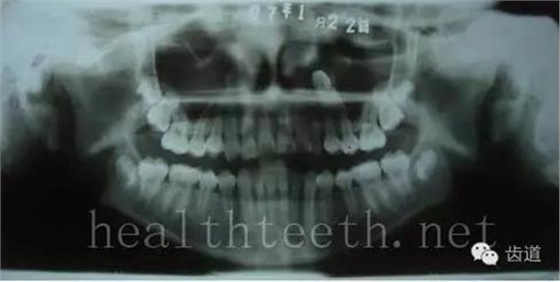

18歲孩子的口腔狀況

30歲人的口腔狀況